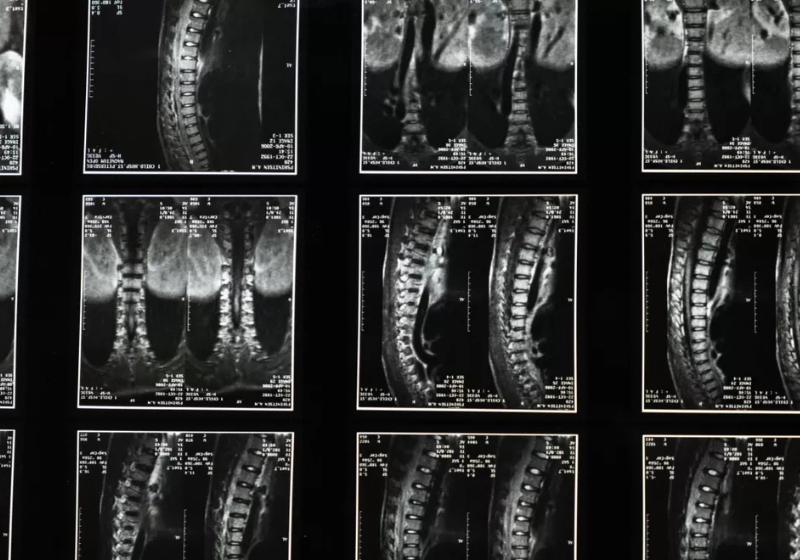

Pela primeira vez, pacientes com lesão na medula espinhal conseguiram recuperar parte dos movimentos após receberem um tratamento com células-tronco no Japão. A notícia boa representa uma esperança para milhares de pessoas no mundo.

Uma equipe de médicos e pesquisadores da Universidade Keio, em Tóquio, anunciou os resultados de um ensaio clínico na semana passada. O experimento usa células-tronco pluripotentes induzidas (iPS) e trouxe melhorias significativas para dois, dos quatro pacientes que participaram do experimento.

A equipe da Universidade implantou as iPS em quatro pacientes que haviam sofrido lesões recentes. Todos eles tinham perdido completamente a função motora em algumas áreas do corpo.

Durante um ano, os pacientes passaram por um processo intenso de reabilitação. Enquanto isso, os médicos monitoravam de perto possíveis reações adversas.

Os resultados foram excelentes. Dois dos participantes conseguiram uma melhora parcial, com destaque para um que se levantou com apoio.

Outro ponto importante foi a segurança do procedimento. Não foram identificados sinais de que as células transplantadas se transformaram em tumores.